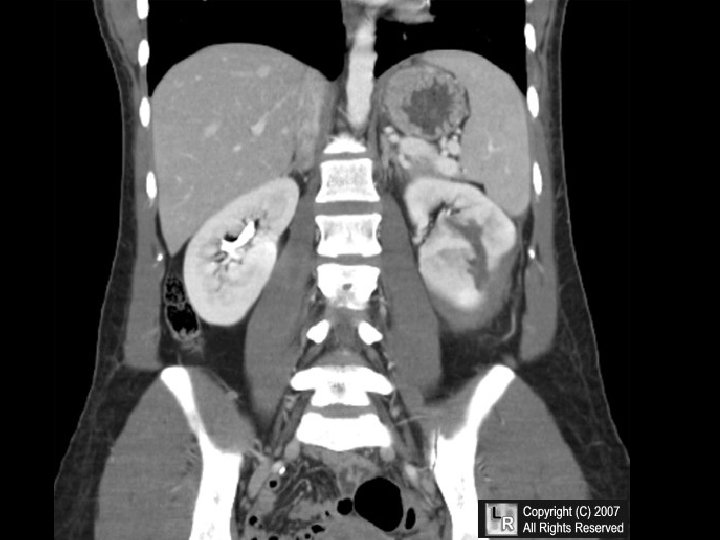

INFARCTION • Defined as an area of necrosis* secondary to decreased blood flow • HEMORRHAGIC vs. ANEMIC • RED vs. WHITE – END ARTERIES vs. DUAL ARTERY SUPPLY • ACUTE ORGANIZATION FIBROSIS

INFARCTION FACTORS • NATURE of VASCULAR SUPPLY – Single end arteries such as kidney, spleen? – Dual blood supply such as lung, liver? • RATE of DEVELOPMENT – SLOW (BETTER) – FAST (WORSE) • VULNERABILITY to HYPOXIA – MYOCYTE vs. FIBROBLAST • CHF vs. NO CHF